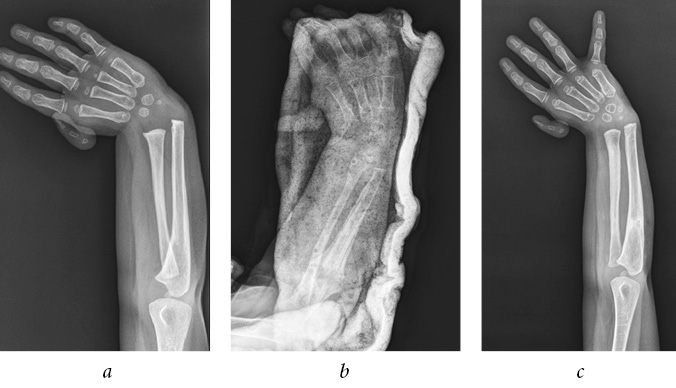

Patient A., 4 years old, was admitted to the department with diagnosis of congenital right-sided radial clubhand, i.e., hypoplasia of the first finger. He did not receive conservative or surgical treatment in a primary care facility. During clinical examination, right forearm shortening by 3 cm was noted, radial deviation of the hand was approximately 45°, the hand could not be passively brought to middle position, and first ray hypoplasia was observed (Fig. 2 a). Given the mild shortening of the radial bone compared with the ulnar bone and satisfactory development of the radial bone, it was decided to restore the radial bone by compression-distraction osteosynthesis. In the postoperative period, inflammation was registered around the exit site of transosseous elements, which were stopped by dressings with surface antiseptics and intake of oral antibiotics.

Fig. 2. Radiographs of the forearm of patient A., (a) 4 years before the surgical treatment, (b) after dismantling the external fixation device, and (c) after 1 year

After the removal of the external fixation device, thinning of the radial bone was established (Fig. 2 b). At 1-year follow-up, recurrence of hand deviation and shortening of the radial bone were registered (Fig. 2 c).